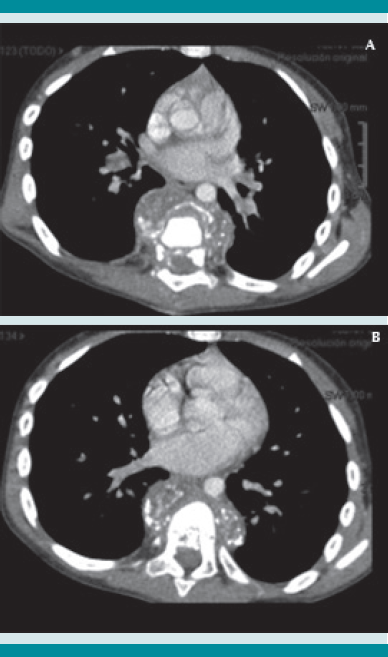

A su ingreso al Instituto Nacional de Pediatría se llevó a cabo el protocolo multidisciplinario hospitalario, que incluye la revisión por parte de los especialistas en oncología, radiología, ortopedia e infectología. En los estudios de imagen se evidenció una lesión anterior a los cuerpos vertebrales de T7-T8 de características líquidas y reforzamiento en la periferia, con destrucción de los cuerpos vertebrales de T7 y T8 a expensas del colapso vertebral que desplaza la médula espinal, con primera posibilidad diagnóstica de tipo infecciosa (espondilodiscitis). Se inició el protocolo de estudio.

La tomografía axial computada de alta resolución puede demostrar lesiones de la primoinfección o linfadenopatía, aun cuando la radiografía de tórax se reporte normal.13 La resonancia magnética se utiliza en mayor medida para la tuberculosis músculo esquelética y de tejidos blandos y, como en este caso, para diferenciar una tumoración de un granuloma en la columna vertebral.14 Otros métodos, como la gammagrafía, que con marcadores como Tecnecio 99 tiene una especificidad de 30% y con galio de 70%. El SPECT y PET tienen mejor especificidad que la tomografía o gammagrafía para discernir entre tuberculosis y lesiones cancerosas,15 con un valor predictivo negativo mayor de 90%, a diferencia de pacientes con tuberculosis pulmonar, además de mayor captación e identificación de lesiones óseas se puede utilizar como auxiliar en tuberculosis extrapulmonar. Finalmente, pueden ser de gran ayuda para determinar el grado de actividad de la enfermedad y la respuesta al tratamiento indicado.